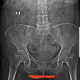

Kedua mengenai pemeriksaan dok, sebenarnya sudah saya sarankan, cuma alasan pasien adalah keterbatasan biaya dok, untuk sementara menyingkirkan kemungkinan OA hip yg saya pikirkan pertama adalah AP untuk sekaligus melihat hip joint kanan nya dok, mungkin dilain kesempatan akan dikembangkan ke lateral atau mobile nya dok.